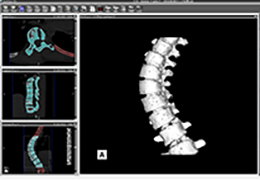

Diffusor Tension Imaging (DTI) module to analyze diffusion-weighted MRI data including calculation of FA maps, fiber tracking and FA group comparisons.

Data analysis includes preprocessing, correlation analysis, determination of Talairach coordinates, volume rendering, surface rendering and cortex flattening.

Segmentation

Segmentation of tissue (e.g., isolating the brain, differentiating gray and white matter) is performed using region-growing methods, filter operations as well as the application of 3D templates. Using the mouse it is very easy to explore a 3D volume with superimposed pseudocolor-coded statistical maps in a four-window representation showing a sagittal, coronal, transversal and oblique section. Based on a (segmented) 3D data set a three-dimensional reconstruction of the subjects' head and brain can be calculated and displayed from any specified viewpoint using volume or surface rendering.

Volume Rendering

Volume rendering is performed with a very fast ray casting algorithm; lightning calculations are based on Phong-shading. Surface rendering of reconstructed surfaces is performed using OpenGL. Using texture mapping, a reconstructed surface (e.g., head or brain) may be sliced in real time, showing both surface and volume data at the same time. Initial polygon meshes serve as the basis for surface finding, cortex inflation and cortex flattening computations.